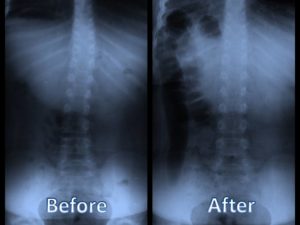

Child's_scoliosis_before_and_after_chiropractic